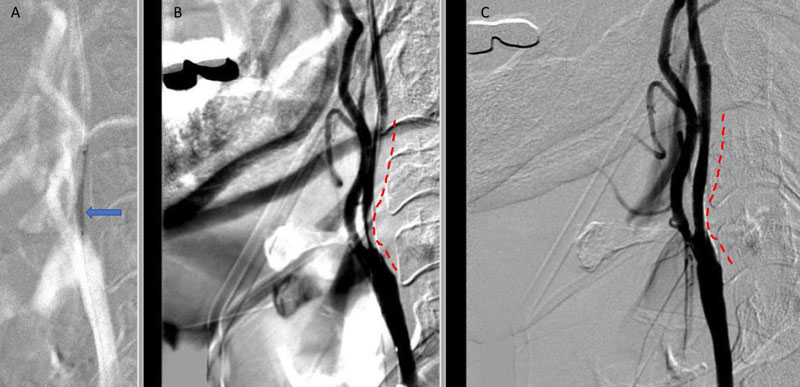

Under Monitored Anesthesia Care, and systemic anticoagulation (ACT maintained above 250), a 6 French Guide Sheath was positioned within the distal cervical right Common Carotid Artery (CCA). Slow antegrade filling of the right internal carotid, MCA, and ACA was observed compatible with flow limitation, as well as physiologic need for this relatively isolated circulation. In addition, primary embolic protection filter placement was not considered technically feasible secondary to the severity of the “string” like stenosis. Serial primary angioplasty with 2 x 20 mm and a 2.5 x 20 mm balloon was gently performed to 10-12 ATM, creating an improved channel within the stenosis. An exchange length .014 (300 cm) “buddy” wire was then positioned across the lesion to maintain access, as an embolic protection filter was carefully navigated and deployed in the distal cervical ICA. Subsequently, a 4 x 40 mm PTA balloon was then utilized to perform angioplasty with embolic protection, followed by placement of a 40 mm stent tapering from 6 to 8 mm from distal to proximal within the right ICA and CCA. Post Stenting angiography demonstrates no significant residual stenosis with significantly enhanced right hemispheric perfusion on angiography (Figure 5).

Figure 5. A) Pre-Dilatation with 2.5 x 20mm balloon (arrow) ; B) Initial PTA result with “Buddy Wire”; C) final Post PTA and Stent with no significant residual stenosis across the entire length of the atherosclerotic segment (dotted).